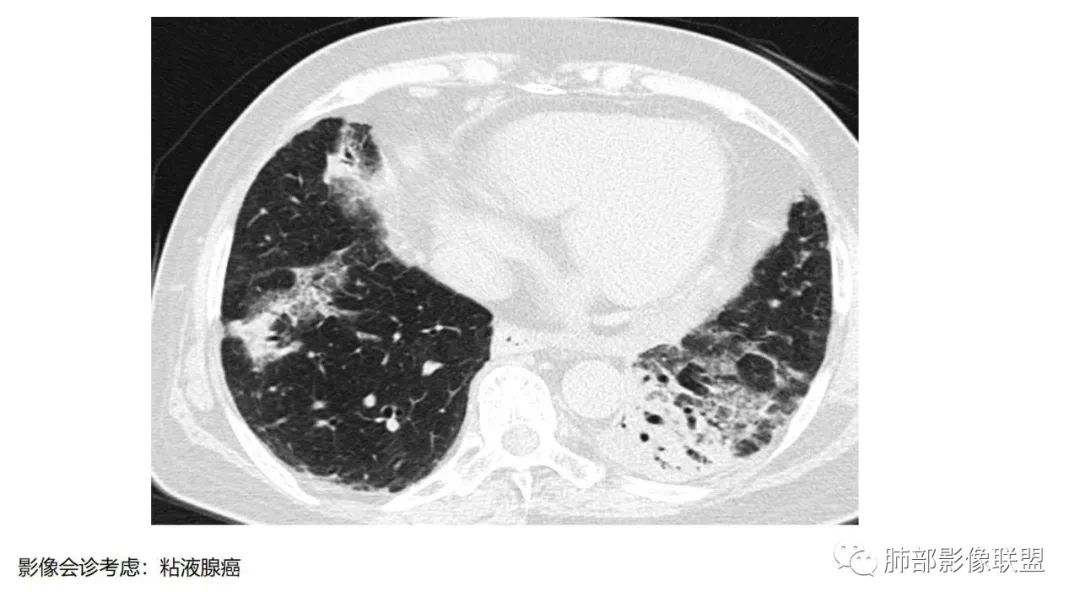

粘液腺癌影像上分为:结节型及斑片型/混合(肺炎型)。

二、肺炎型

2、病灶常有一个主病灶,常位于下肺。后沿气道播散为多发病灶。

3、重力作用,叠瓦征。近叶间裂因重力效应,呈膨隆改变。

4、增强后不均匀强化,存在低强化区呈弱强化或无强化,因此可见“血管造影征。”血管毛糙与肺炎有统计学差异。

5、支气管粗细不均,呈“枯树枝征”,但与肺炎这一点鉴别不具有统计学差异。可发生支气管扩张

6、空腔形成,部分蜂窝状改变。

8、斑片常伴有结节,边缘清楚GGO或欠清楚。